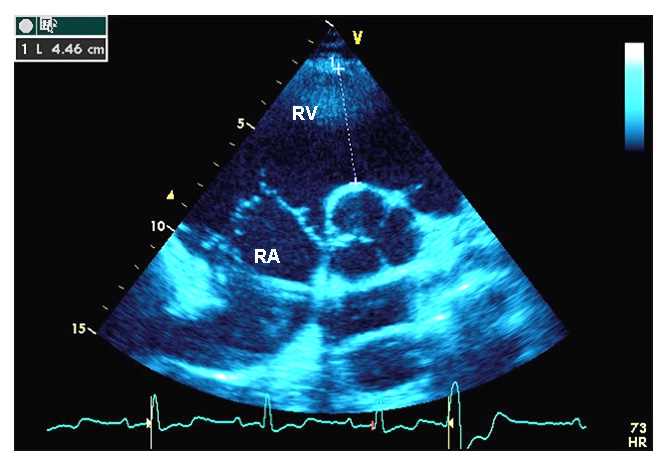

Figure 2

Transthoracic echocardiography, and genetic screening of case 2.

A Parasternal short axis view. Right atrium and right ventricular infundibulum are indicated. The right ventricular infundibulum diameter is measured at the level of the aortic valve.

RA = right atrium; RV = right ventricular infundibulum.